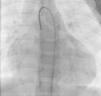

Os motivos de referência mais frequentes foram sopro e/ou cansaço. Todas as fístulas eram de origem congénita. Cinco doentes (42%) tinham patologia cardíaca concomitante: atrésia da pulmonar com septo interventricular intacto (1), canal arterial persistente (1), comunicação interauricular ostium secundum (1), estenose aórtica em válvula aórtica biscúspide (1), estenose pulmonar crítica operada no período neonatal (1). Foram realizadas angiografias selectivas para delinear a anatomia da(s) fístula(s). A embolização foi feita na porção mais distal da fístula, poupando todos os ramos colaterais. Num doente foi realizada uma ansa arteriovenosa através da fístula, com embolização da porção terminal da fístula a partir da aurícula direita. Os doentes foram heparinizados (100 U.I./kg na criança e 5000 U.I. no adulto) e foi feito o controlo posterior através do valor de ACT. Três dos doentes apresentavam duas fístulas e os restantes comunicações fistulosas isoladas. As fístulas eram todas hemodinamicamente significativas e tinham origem no território da coronária direita (n=10), da coronária esquerda (n=3) e da circunflexa (n=2) e drenavam para o ventrículo direito (n=5), artéria pulmonar (n=6), aurícula direita (n=2), seio coronário (n=1) e ventrículo esquerdo (n=1). O material de embolização incluiu 15 coils standard em 3 doentes, 1 coil Jackson® num doente (Figuras 1–3), 27 microcoils em 11 doentes (18 microcoils simples em 7 doentes e 9 microcoils GDC em 4 doentes) e um dispositivo Amplatzer®Duct Occluder num doente (Figuras 4–7). Merece um destaque especial os microcoils GDC, simples ou complexos, que são dispositivos de libertação controlada por electrólise, o que permite que o procedimento seja reversível até à fase final da libertação, após se confirmar a boa posição do dispositivo. Num doente foi testado um plug cardíaco Amplatzer® que não foi libertado por não ser adequado à lesão.

A abordagem clássica da fístula coronária é o encerramento cirúrgico. Em 1997, Mavroudis et al apresentou uma análise sobre resultados cirúrgicos de encerramento de fístulas coronárias em 17 doentes com idades compreendidas entre as seis semanas e os 16,5 anos (idade média 5,5 anos) e tratados entre 1968 e 1996, concluindo que o encerramento cirúrgico de fístulas coronárias foi 100% eficaz e sem mortalidade naquela série, pelo que deve ser o tratamento de eleição nestas situações, devendo o encerramento percutâneo ficar reservado para apenas uma pequena população seleccionada11. Contudo, já em 1991, tinha sido descrito o encerramento percutâneo de sete fístulas coronárias em doentes com idades compreendidas entre os dois e os 67 anos (idade média de 17 anos), que decorreu com sucesso em seis das sete fístulas encerradas e sem complicações durante um tempo de seguimento de quatro meses a quatro anos12. Neste artigo, os autores chamam a atenção para a vantagem do encerramento percutâneo com a possibilidade de se evidenciarem fístulas adicionais após o encerramento da(s) fístula(s) de maiores dimensões apenas visível(is) no encerramento percutâneo. Apesar de tecnicamente mais difícil, fístulas de grandes dimensões a drenarem para a aurícula direita ou para o ventrículo direito podem ser encerradas por via venosa com dispositivos como Amplatzer®Duct Occluder ou plugs, com monitorização do posicionamento adequado do dispositivo através de injecções selectivas retrógradas na artéria coronária, como descrito em 2000 por Pedra et al5 e realizado no nosso caso 9 (Fig. 1 a 4).